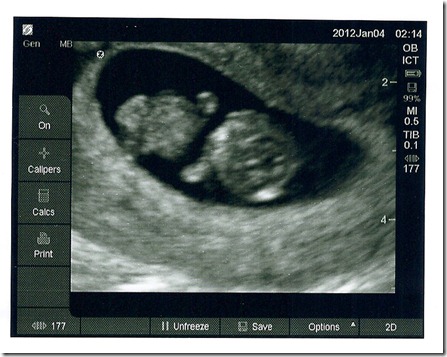

And . . .  Introducing our little peanut:

They did change my due date a  couple of days, which is fine. But I got to see my little baby moving its hands around, and the little heart fluttering, and I’m already in love!

For those not fluent on your fuzzy dots, I edited the picture for you (it’s SO much easier to see in person than in a picture! and the other leg is hiding behind the cord right now, but it’s there!)